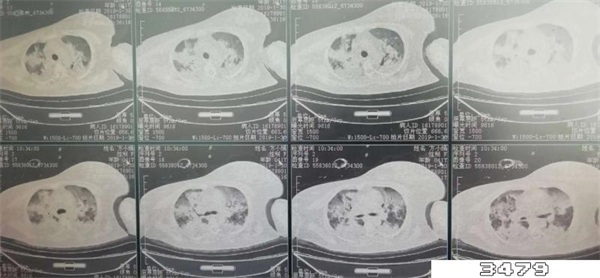

新官白肺病的症状包括缺氧、胸闷、呼吸窘迫、呼吸困难、紫绀、严重低血氧症,严重的话可能会出现呼吸衰竭、昏迷的情况。导致白肺的原因一般是肺部细菌感染或人体炎症反应,形成大白肺的情况一般都表示肺部被炎症所广泛浸润。

形成白肺一般说明肺部的炎症较重、肺部渗出液较多。但是随着渗出液的吸收、炎症的消退,白肺的表现也会逐渐消退。并不是说只要肺部出现了炎症就都叫“白肺”,白肺实际上是一个比较严重的肺炎表现。